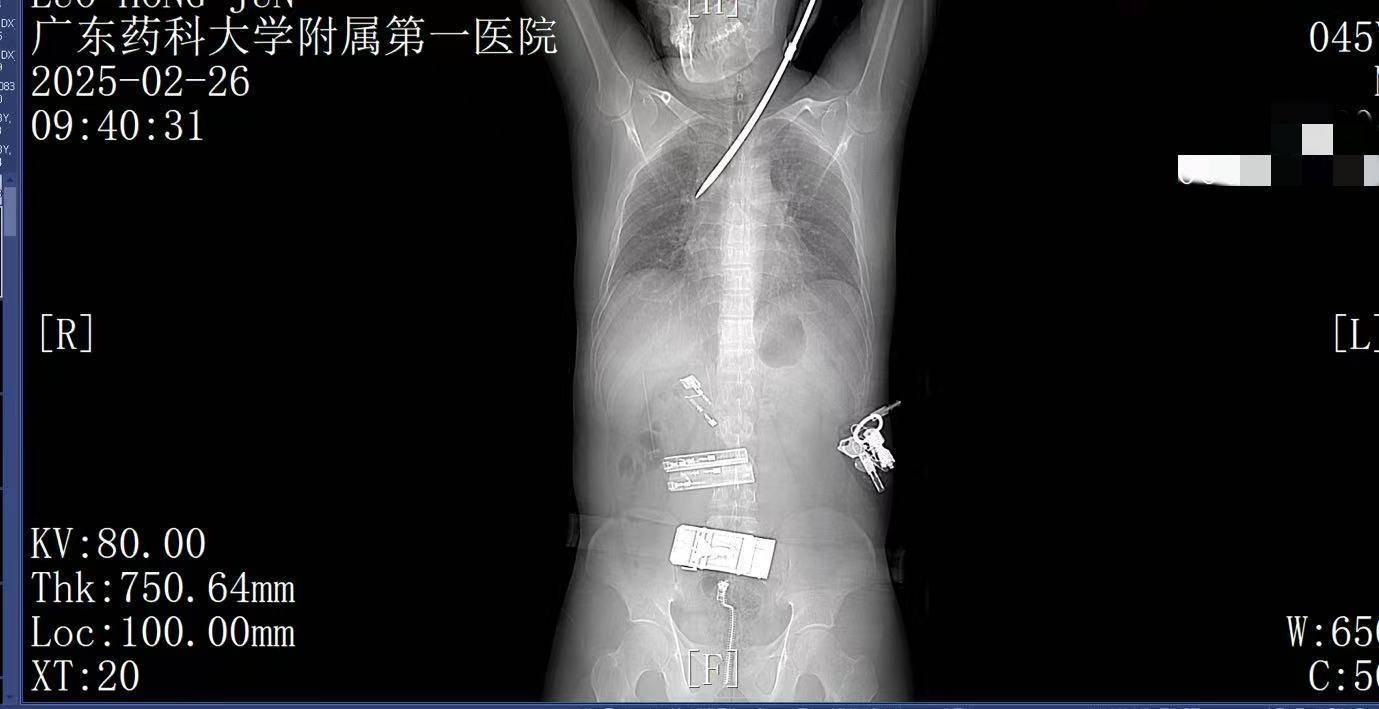

9:41,快速完成头+胸+腹部CT检查,经多学科会诊,明确螺丝刀异物刺入肺部区块链虚拟币。CT显示螺丝刀紧贴肋间血管、上肺后段动脉,尖端距右肺门仅2厘米,一旦贸然拔出螺丝刀,极有可能引发大出血,导致失血性休克甚至死亡,必须紧急手术。

9:39,救护车到达医院大门,院内急救团队已经做好准备区块链虚拟币。在紧密监护的情况下,全程采用绿色通道。到达医院时,罗师傅已经面色苍白,呼吸急促。螺丝刀已深深刺入罗师傅右肺,随时可能因大出血而危及生命。